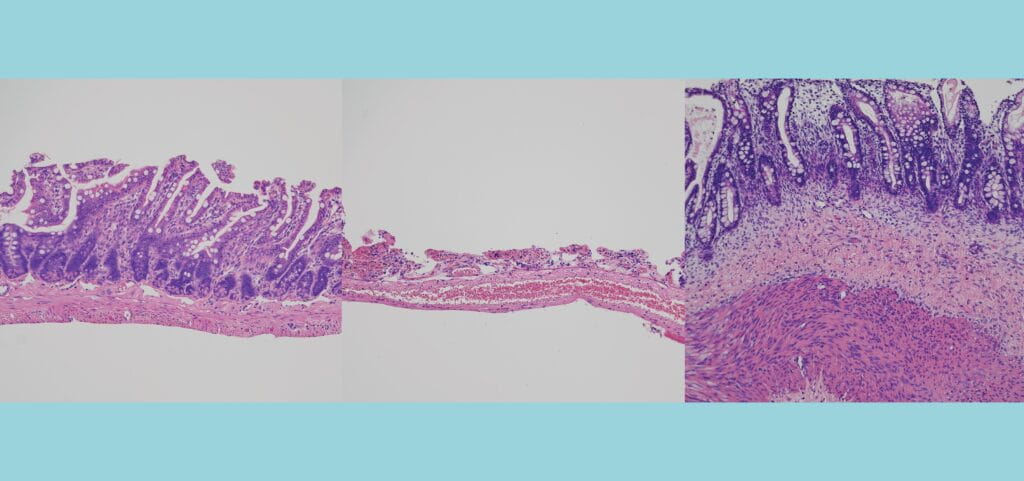

As a pediatric surgeon scientist, Dr. Helmrath has established a large multidisciplinary team dedicated to clinical, translational, and basic science research focused on human diseases. Clinically, he is dedicated to patients with intestinal diseases and obesity. In his laboratory he focuses on characterizing intestinal stem cells during intestinal adaptation and developing intestinal regenerative strategies. He has expertise in the generation of stem cells and the development of organoids. His strong basic science research background further allows him to translate human GI conditions to the laboratory to develop highly innovative approaches to treat intestinal diseases.